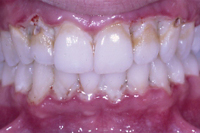

Die Abb. 1 bis 4 sollen als anschauliche Beispiele für gesunde und kranke Fundamente dienen.

Ein 31 Jahre alter Patient zeigt einen starke Zahnfleisch-Rückgang im Oberkiefer (Abb. 1 und 3) und wir beschliessen, diese Rezessionen zu behandeln.

Der Erfolg der Behandlung ist deutlich in den Abb. 2 und 4 zu sehen. Sehr augenfällig konnte die Situation um den Eckzahn im linken Oberkiefer verbessert werden (vergleiche dazu Abb. 3 vorher und Abb. 4 nachher).